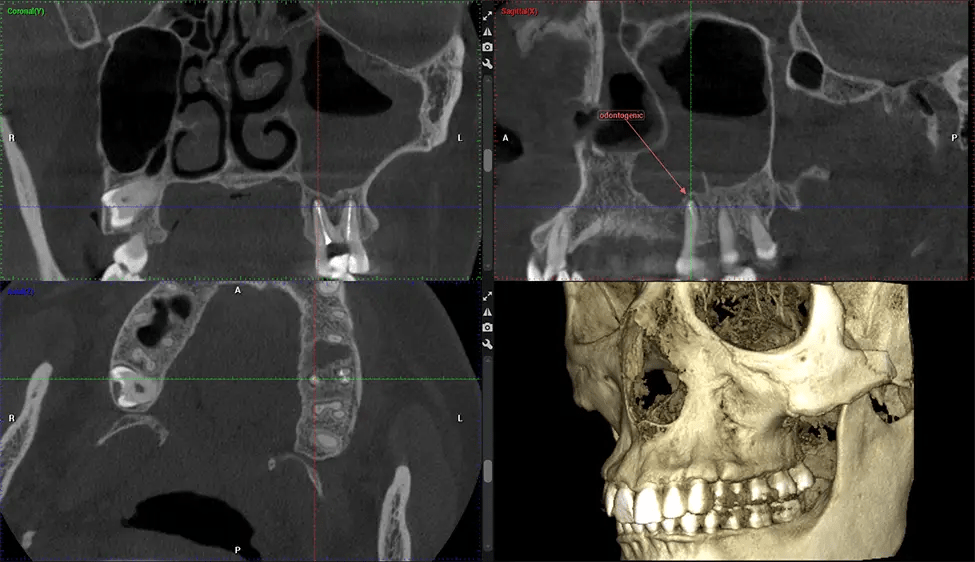

Esta exploración 3D, llamada tomografía computarizada de haz cónico, le brinda a su dentista una imagen más completa de su anatomía bucal y sus procesos patológicos que una radiografía tradicional. A diferencia de las radiografías convencionales, que capturan una imagen 2D de la boca desde varios ángulos, una exploración 3D toma varias radiografías digitales para una imagen. Proporciona una vista completa de la mandíbula, los dientes, los nervios y los tejidos blandos. Esta vista mejorada permite a los dentistas detectar problemas menores que no son visibles en las exploraciones 2D tradicionales, como muelas del juicio impactadas o fracturas óseas en la cavidad sinusal.

Existen muchos beneficios al utilizar la tecnología CBCT, especialmente en comparación con el formato tradicional de rayos X 2D. Una de las ventajas más importantes de las exploraciones CBCT es que proporcionan mucha más información que las radiografías tradicionales. Una exploración le permite a su dentista ver imágenes desde todos los ángulos de su mandíbula y boca, incluidos los senos nasales, la cavidad nasal, los pómulos y otras áreas circundantes. Esta información adicional ayuda a su dentista a elaborar un plan de tratamiento integral que aborde todos los aspectos de su salud bucal.

Otro beneficio importante es que las imágenes 3D proporcionan imágenes más precisas de la estructura ósea. Estas imágenes son más detalladas y le brindan un diagnóstico más preciso. Un diagnóstico preciso significa un mejor tratamiento para usted.

Después del proceso de escaneo, las imágenes de rayos X capturadas son procesadas por el software CBCT, que aplica algoritmos para reconstruir una imagen 3D detallada del área escaneada. El software recopila estas imágenes de rayos X individuales y crea una representación digital en 3D de la anatomía del paciente. El dentista o el radiólogo pueden ver y analizar la imagen CBCT 3D reconstruida. Esta imagen se puede manipular, rotar y acercar o alejar para examinar estructuras específicas y evaluar la condición del paciente.